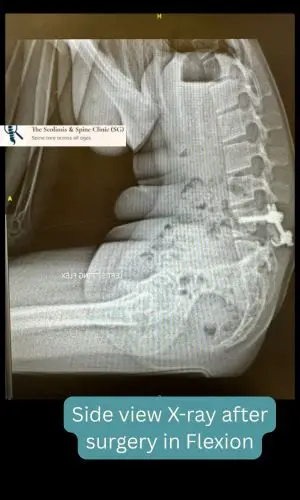

Despite three months of non-operative management, her ache persisted. A decision was made to proceed with surgical repair- a non-fusion motion preserved technique – using direct pars fixation—a targeted approach to stabilize the fracture and restore spinal integrity while maintaining the flexibility.

Side view radiograph of the lower back in flexion confirms segmental stability at the site of previous fracture.